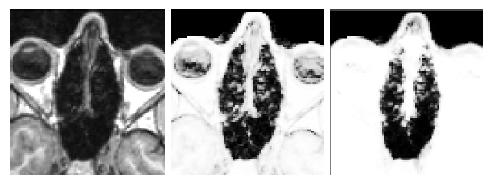

Results of atlas-based segmentation of structural MR is shown in Fig. 5 below.

T1 of the sinus region is shown on the left. The limitations of using the intensity

classifier to segment the MR is shown in the middle image. While the classifier produces reasonable results for many of the voxels in the sinuses,

voxels outside this region which are clearly soft tissue or

bone are mislabeled with values close to zero. In contrast, using the atlas-based

segmenter (right image) achieves similar results for the highly variable

subject-specific anatomy within the sinus region, while producing fewer errors

in the surrounding area.